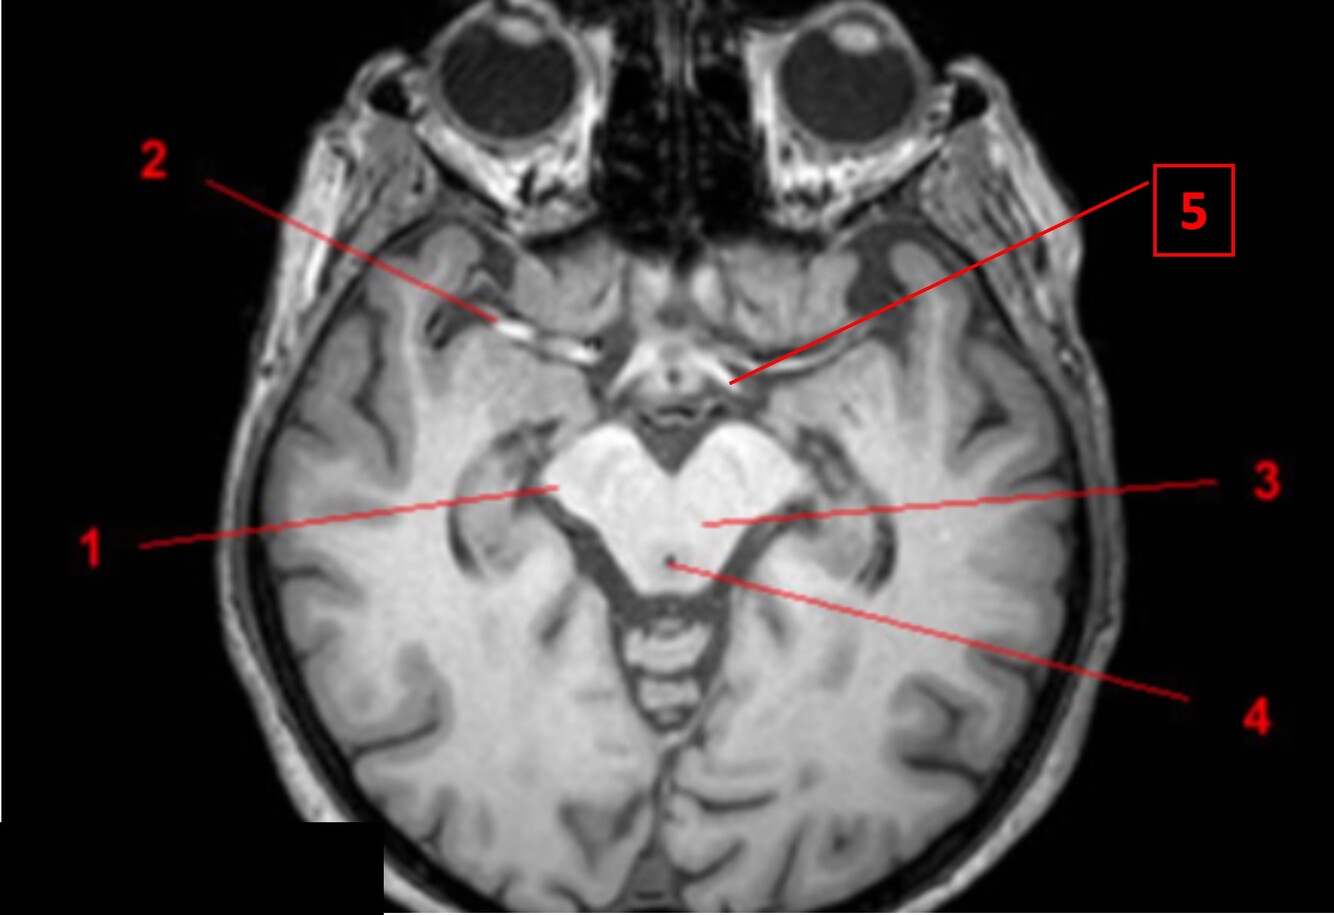

Q

Label 1-5

A

1. Rt cerebral peduncle of midbrain

2. Rt middle cerebral artery

3. Midbrain

4. Cerebral aqueduct

5. Lt optic tract

How well did you know this?